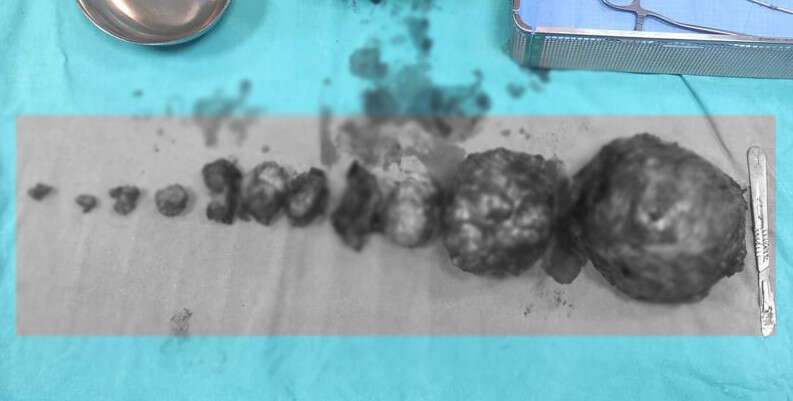

Van’da erken doğum riski nedeniyle hastanede takip edilen kadının rahminden en büyüğü 20 santimetre olmak üzere 5 kilo ağırlığında 13 adet miyom başarılı bir ameliyatla çıkarıldı.

İpekyolu ilçesinde yaşayan Hülya Arvas isimli hamile kadının rahminde çok sayıda miyom tespit edildi. Doktorlar tarafından yapılan ilk muayenede, miyomlar nedeniyle bebeğin düşük riski olduğu ve rahminin de alınabileceği değerlendirildi. Van Eğitim ve Araştırma Hastanesinde düşük tehlikesiyle yatan Arvas, 31 haftalık hamileyken doğum sancıları nedeniyle acil bir şekilde ameliyata alındı. Burada Kadın Hastalıkları ve Doğum Uzmanı Dr. Erhan Hanlıgil ve Op. Dr. Ayşe Yavuz tarafından ameliyata alınan anne, 1 kilo 400 gram ağırlığında bir bebek dünyaya getirdi. Daha sonra doktorlar tarafından kadının rahmi alınmadan yaklaşık 5 kilogram ağırlığında 13 adet miyom da başarılı bir şekilde alındı.

Van’da erken doğum riski nedeniyle hastanede takip edilen kadının rahminden en büyüğü 20 santimetre olmak üzere 5 kilo ağırlığında 13 adet miyom başarılı bir ameliyatla çıkarıldı.

İpekyolu ilçesinde yaşayan Hülya Arvas isimli hamile kadının rahminde çok sayıda miyom tespit edildi. Doktorlar tarafından yapılan ilk muayenede, miyomlar nedeniyle bebeğin düşük riski olduğu ve rahminin de alınabileceği değerlendirildi. Van Eğitim ve Araştırma Hastanesinde düşük tehlikesiyle yatan Arvas, 31 haftalık hamileyken doğum sancıları nedeniyle acil bir şekilde ameliyata alındı. Burada Kadın Hastalıkları ve Doğum Uzmanı Dr. Erhan Hanlıgil ve Op. Dr. Ayşe Yavuz tarafından ameliyata alınan anne, 1 kilo 400 gram ağırlığında bir bebek dünyaya getirdi. Daha sonra doktorlar tarafından kadının rahmi alınmadan yaklaşık 5 kilogram ağırlığında 13 adet miyom da başarılı bir şekilde alındı.